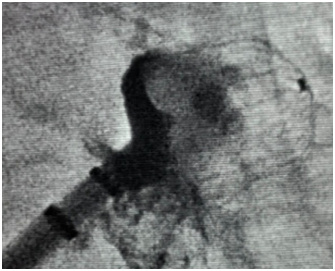

术前基质

术后左右肺静脉验证

消融展示

这项技术的精妙之处在于它的“细胞识别” 能力。它释放的“电脉冲”能精准地只对心肌细胞的“细胞膜”造成不可逆的损伤,形成“电穿孔”,让异常“放电”的心肌细胞“凋亡”(死掉)。而对紧挨着的食管、血管、神经等“无辜邻居”,可降低对周围组织的损伤风险。

无论是85岁基础病多的爷爷,还是食管癌术后的大哥,PFA技术可安全完成核心任务:隔离肺静脉,让心脏电路恢复规律“跳动”。